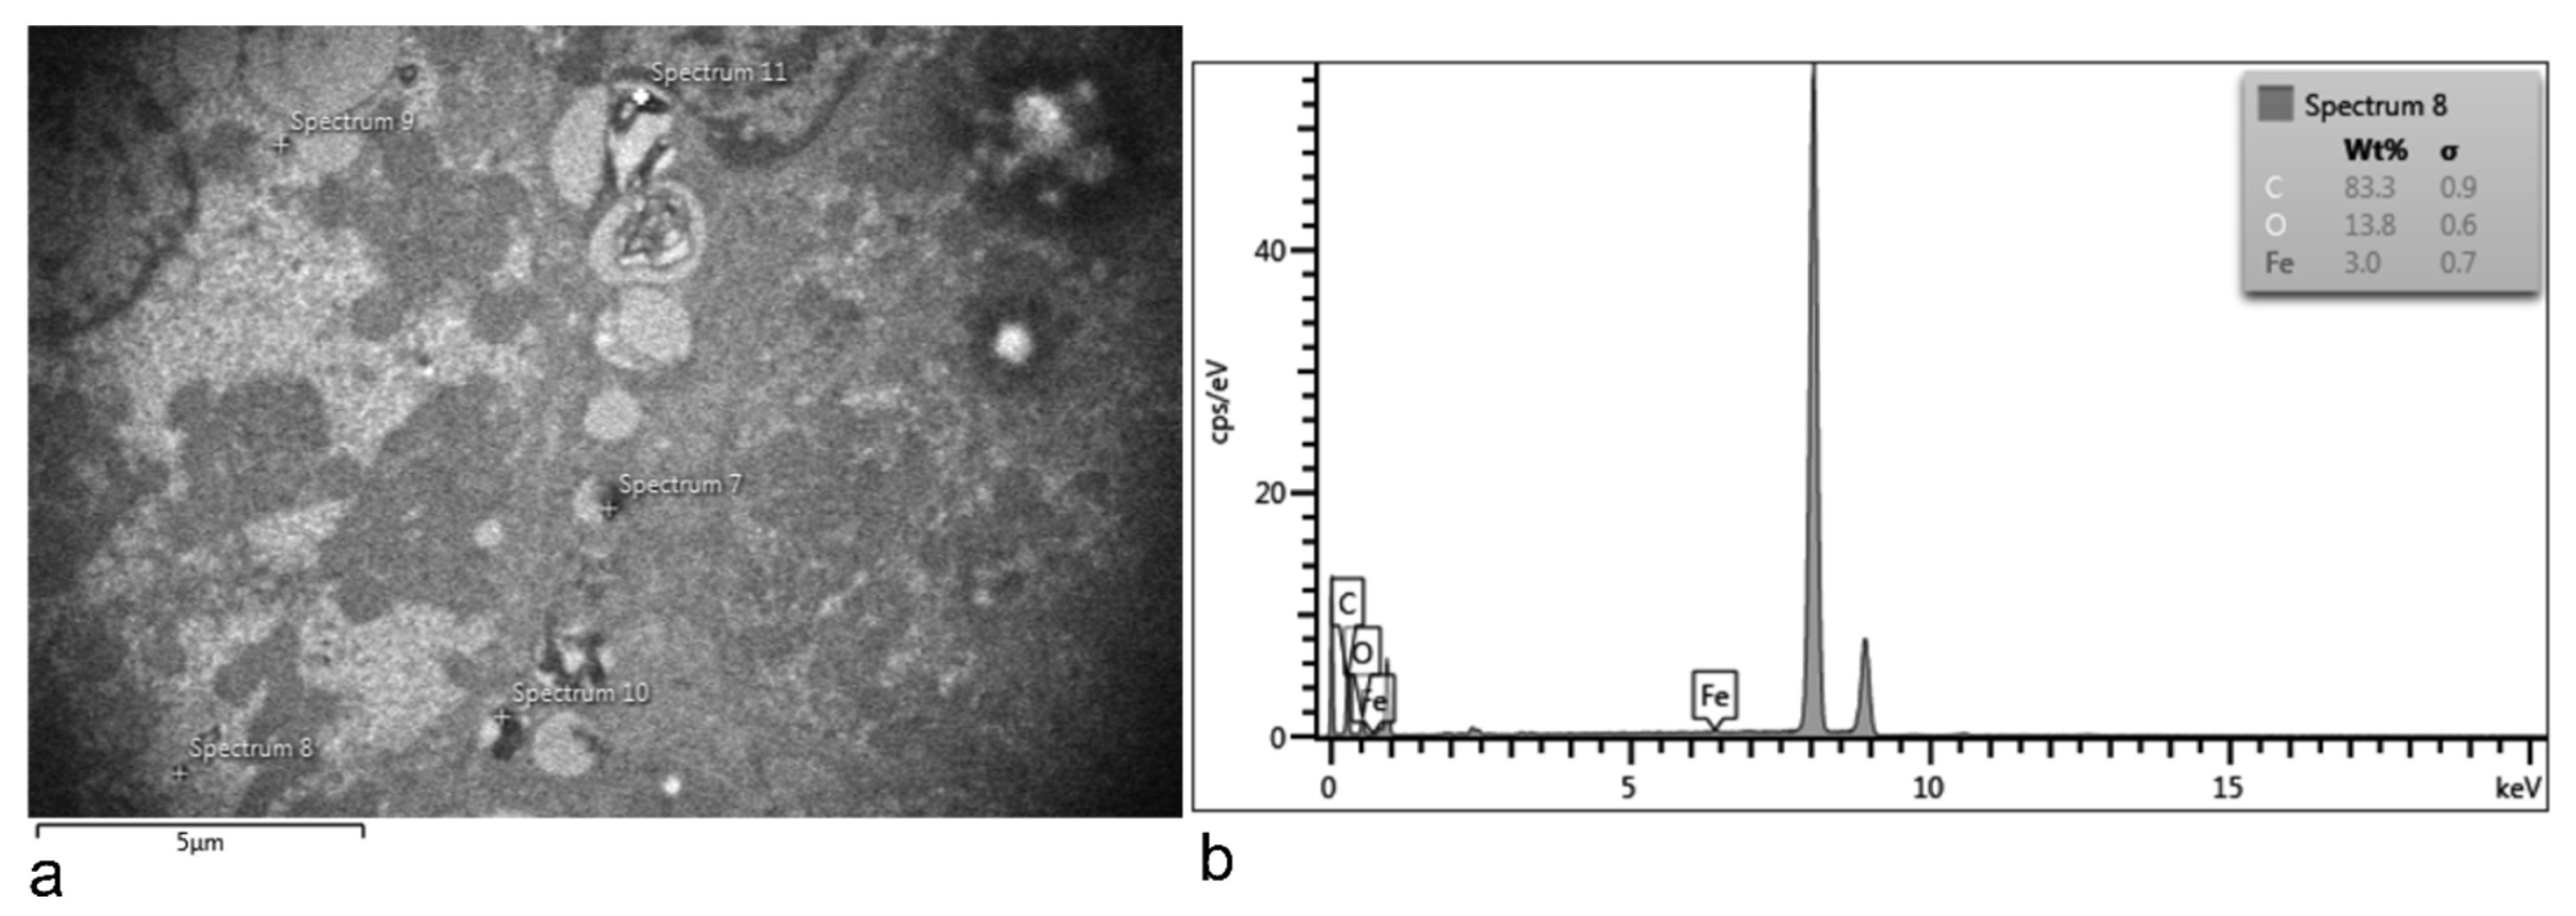

3.1. SPION-PEG Clusters Characteristics

3.5. Electron Microscopy Analyses of Rat Organs